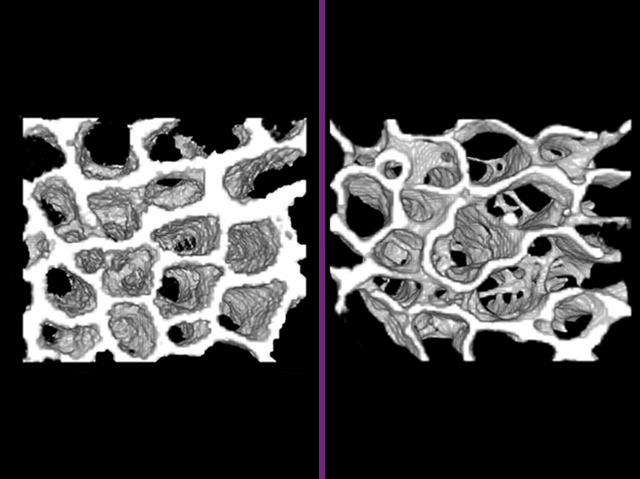

Lower blood pressure, reduced risk of heart disease and decreased stress hormones are not the only medical benefits cats may provide us. A small number of cats develop chronic kidney disease (CKD) and this progresses in a similar way to human CKD. Humans with kidney problems are four times more likely to develop osteoporosis – where the bones become thin and prone to fracture. The same is true of cats, who have a similar bone structure to us. In this study researchers analysed cats that had died naturally from CKD (with permission from their owners). Pictured are CAT scans from cats: on the right, bone from a CKD cat is less dense and has increased numbers of cavities compared to bone from a control on the left. This has helped to understand why the bones are more fragile and will lead to improved treatments for both cats and human with CKD.